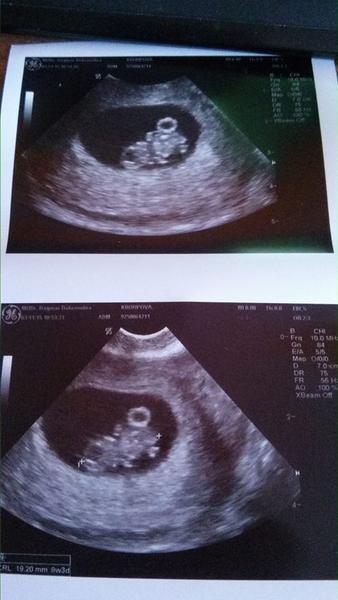

Ahoj, tak se take snazime a mam za sebou druhou insemenaci... Jsem tak napnuta...cekam na 19 teho a budu delat testik (@; mam bolesti v podbrisku... Jsem nervozni. Mela jste to tak nektera ? Jemny tlak... Bolesti trochu jako pred menzesem...